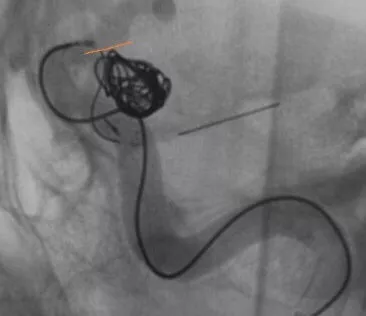

Enterprise4.5×22支架半释放,支架尾端的有效段能恰好覆盖全瘤颈

支架有效段完全释放,这个时候开始将支架导管往前顶,让导管头端尽量越过瘤颈远端

支架完全释放

释放后的造影。突入颈内动脉和后交通动脉内的弹簧圈被压入瘤体内